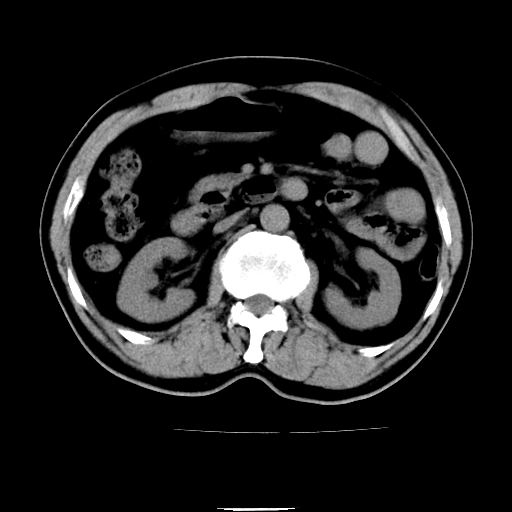

以下是引用chenqiong在2010-3-25 20:56:00的发言:[br]1、胆囊炎,胆囊息肉[br]2、肝内胆管及胆总管扩张,胆总管下端结石[br]3、十二指肠乳头旁憩室

以下是引用zxl51642在2010-3-26 10:47:00的发言:[br]胆囊炎,胆囊息肉,胆总管扩张,但未看到明显肿块,肝内胆管扩张不像恶性,炎性狭窄或阴性结石可能吧,建议mrcp,右肾小囊肿